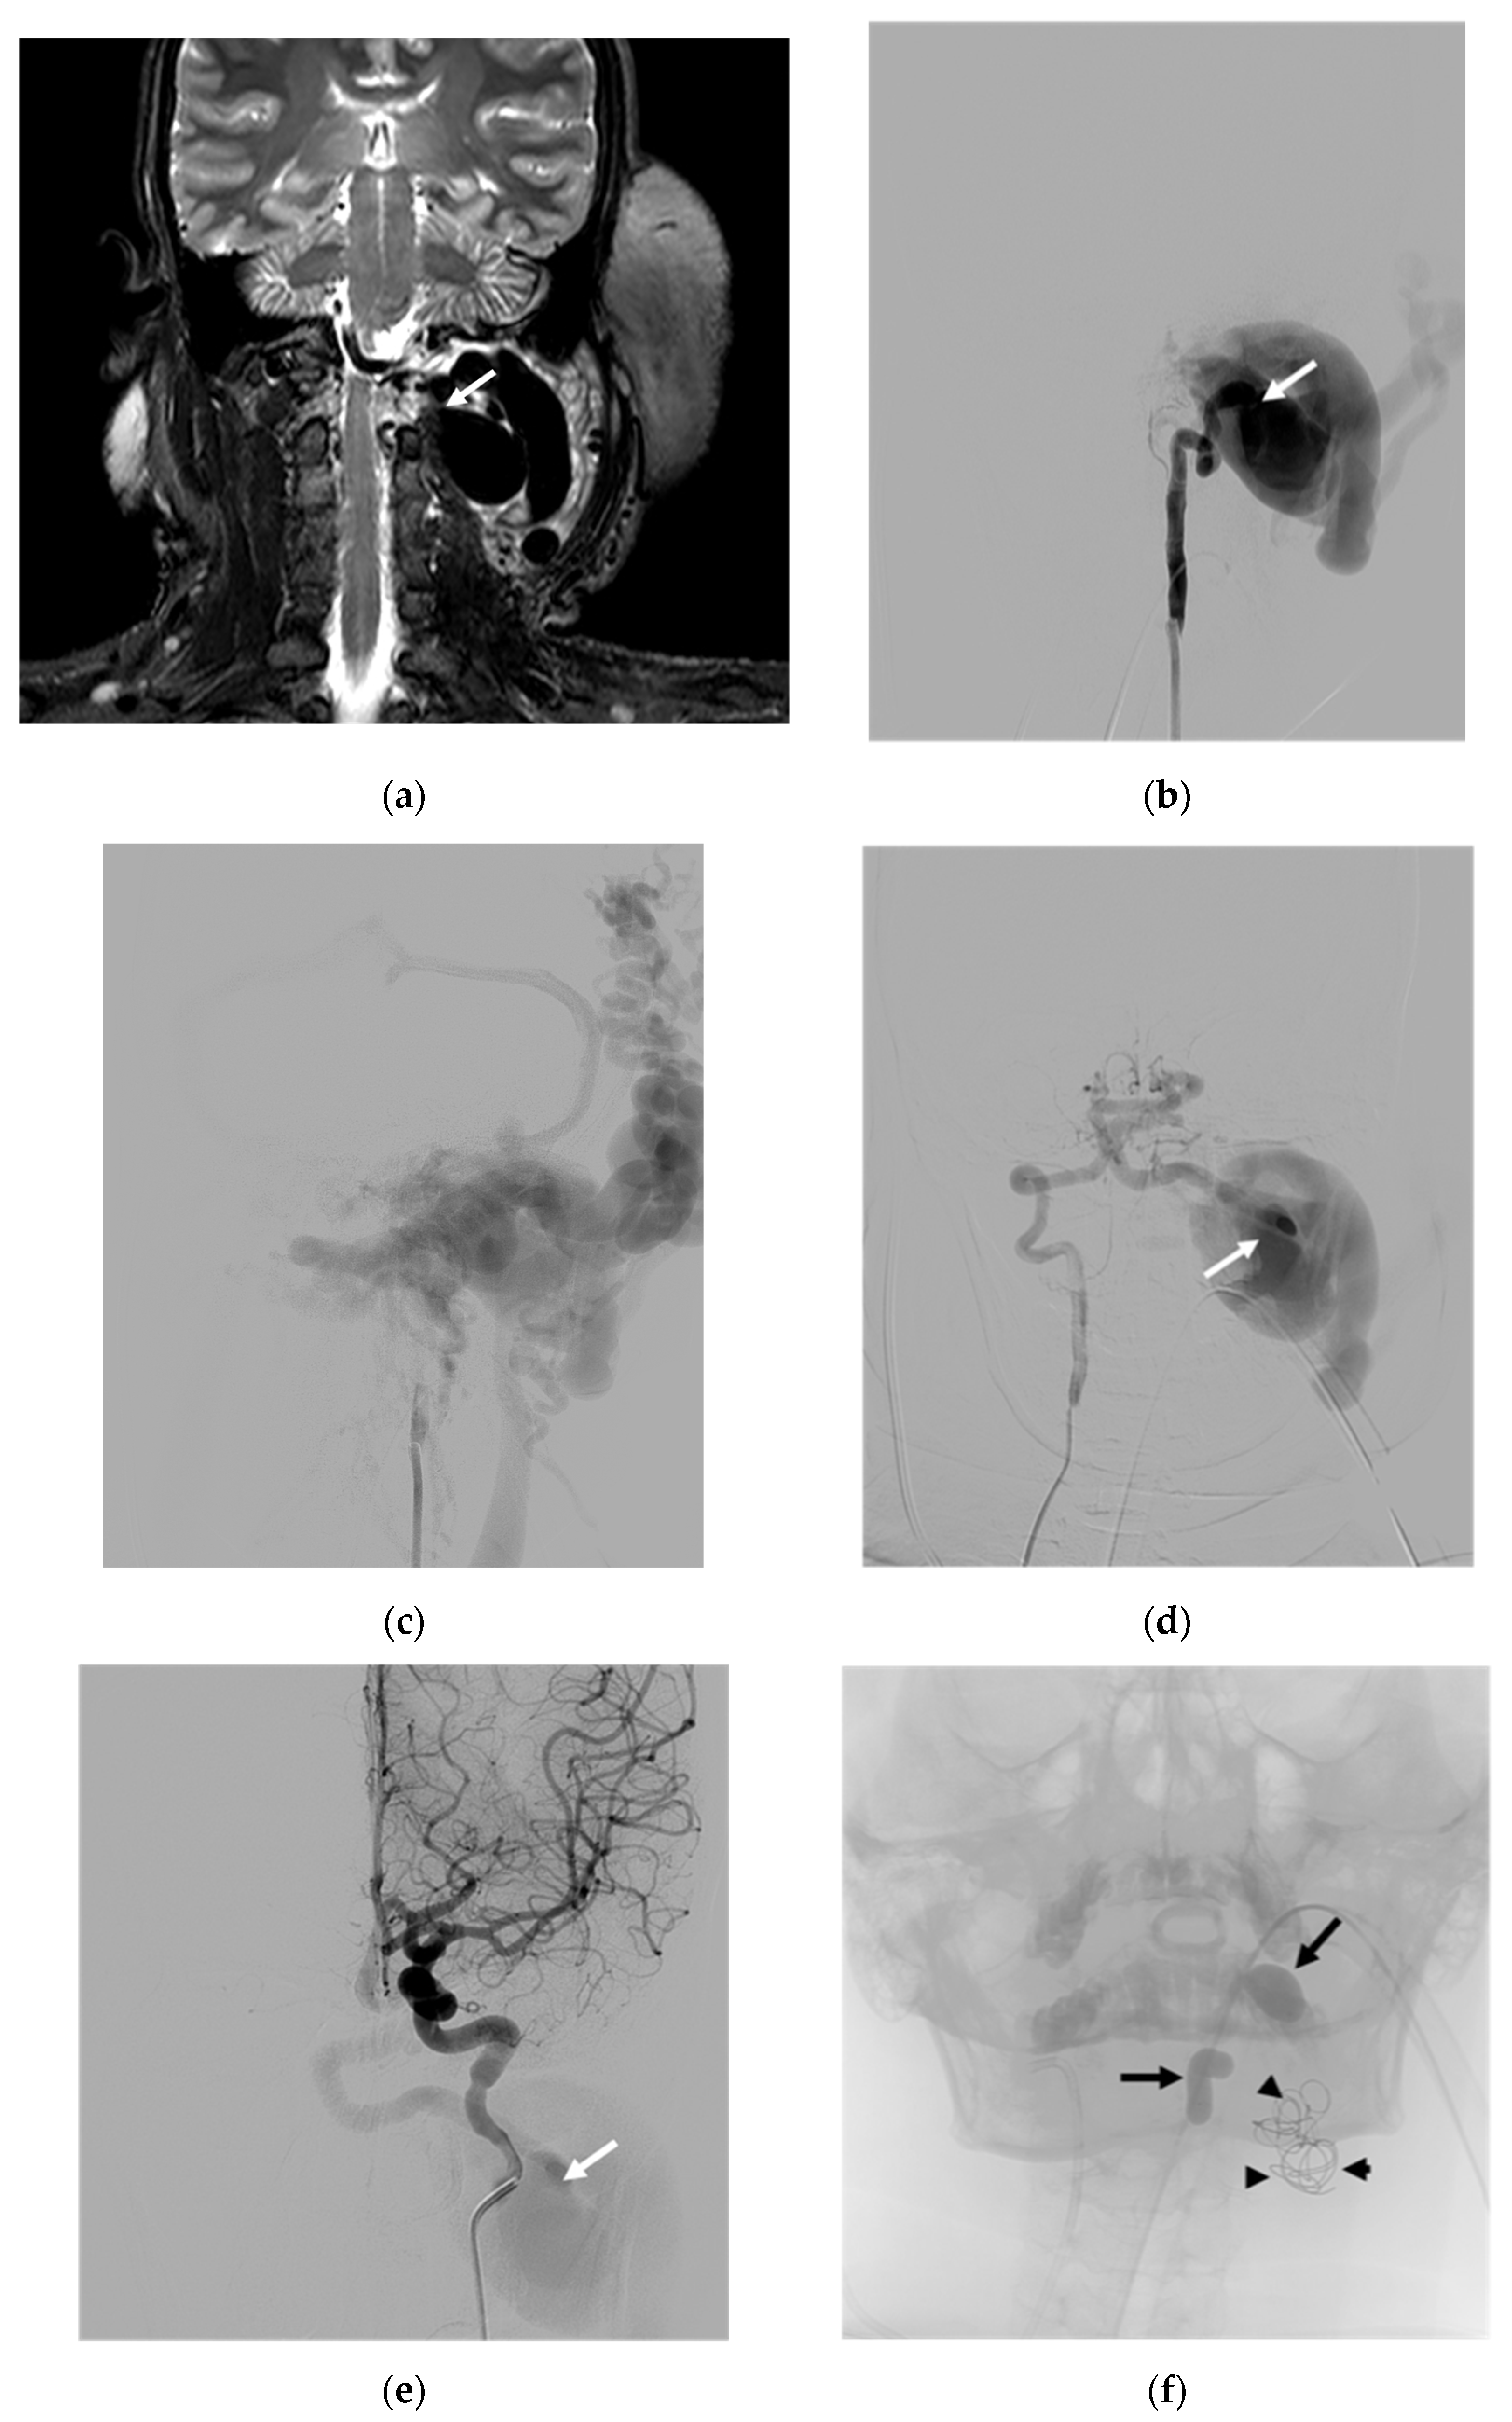

| 1 | F | 49 | Neck mass; tinnitus; right arm weakness | Unknown | S | Radicular vein; VVP with venous pouch | Y | C and NBCA | O | Improved | Transient occipital pain |

| 6 | M | 42 | Proptosis of left eye | Unknown | S | Epidural veins; VVP to IPS; CS and left SOV | N | B and C | O | Improved | None |

| 8 | F | 33 | Neck mass; tinnitus; paresthesia of left arm; ataxia | NF-1 | S | IJV; VVP with venous pouch | Y | B, C, and NBCA | O | Improved | Vertigo |